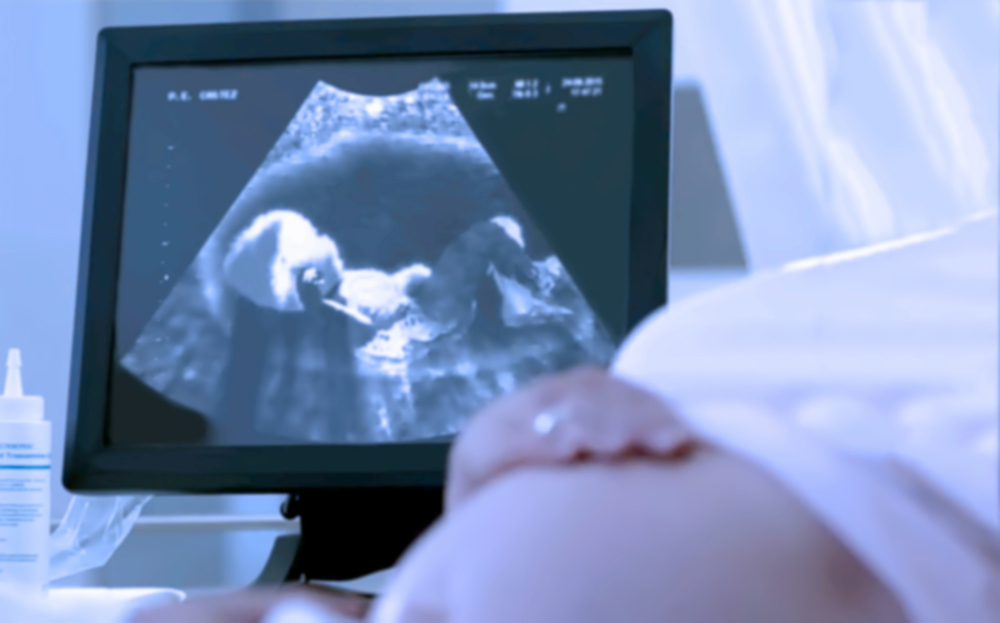

ត្បិតមិនមានមូលហេតុច្បាស់លាស់ តែមានកត្តាប្រឈមផ្សេងៗ ដែលធ្វើឲ្យស្ត្រីពពោះមានសុកពាំងមាត់ស្បូន ដូចជាការពពោះកូនភ្លោះ ពពោះនៅអាយុច្រើន មានកូនញឹកពេក មានដុំស្បូន រលាកដៃស្បូន។ បើតាមការពន្យល់របស់លោកវេជ្ជបណ្ឌិត ចាន់ ស៊ីណេត ប្រធានផ្នែកសម្ភព និងរោគស្ត្រី នៃមន្ទីរពេទ្យមិត្តភាពកម្ពុជា-ចិន សែនសុខ ស្ត្រីពពោះអាចដឹងថាមានសុកពាំងមាត់ស្បូន ឬមិនពាំង ដោយសារការពិនិត្យមើលអេកូពេលមានផ្ទៃពោះ ពិសេសនៅត្រីមាសទី២ ទើបដឹងថាទីតាំងរបស់សុកនៅកន្លែងណា នៅទីតាំងសុវត្ថិភាពទេ? ពាំងចំហៀង ឬក៏ពីមុខមាត់ស្បូន?

ក្រៅពីការមើលអេកូ ករណីសុកពាំងមាត់ស្បូនកម្រិតធ្ងន់ ក៏មានចេញរោគសញ្ញាឲ្យយើងដឹងដែរ ក្នុងនោះមាន ធ្លាក់ឈាមពណ៌ក្រហមព្រឿងៗ ដោយគ្មានការឈឺចាប់ នៅពាក់កណ្តាលត្រីមាសទី២ ឬក៏ស្បូនកន្ត្រាក់។ បើឃើញមានសញ្ញាទាំងនេះ ស្ត្រីពពោះចាំបាច់ត្រូវទៅជួបគ្រូពេទ្យបន្ទាន់។